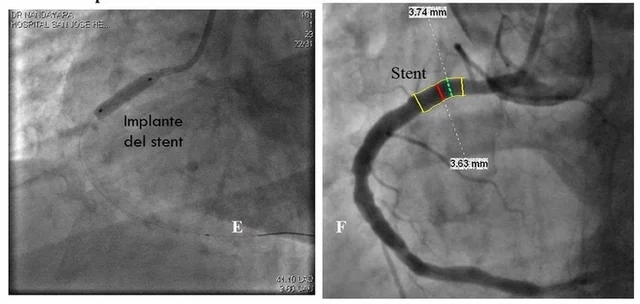

• El primer stent

El primer stent

lo implanto el Dr. Sigwart en Suiza. y en los años subsecuentes el uso del stent supero sus debilidades y demostró su beneficio.

• ya se implantaban stent en más del 80% de los casos de angioplastia con balón.

Un problema de los stent de metal es la cicatrización que hasta en un 30% causa nueva obstrucción (reestenosis) y disminuía el éxito de la dilatación.

• se comenzó a utilizar stent liberador de fármacos (rapamicina o paclitaxel)

modificaban la respuesta de cicatrización y disminuir la reestenosis con lo que aumento el éxito de los procedimientos de intervención coronaria percutánea. La cardiología intervencionista es uno de los campos de la medicina que más ha evolucionado en los últimos años posicionándose dentro de los estudios mas frecuentes realizados en todo el mundo, su explosivo crecimiento en parte es por la alta frecuencia de la enfermedad cardiaca en todo el mundo.

Esta técnica Cambio el abordaje de la enfermedad ateroesclerosa cardiaca e isquémica. La intervención coronaria supero debilidades iníciales y su aplicación se extendió a todo el mundo. Pero sin lugar a dudas el principal factor que contribuyo a su crecimiento fue el uso de endoprotesis coronarias o Stent.